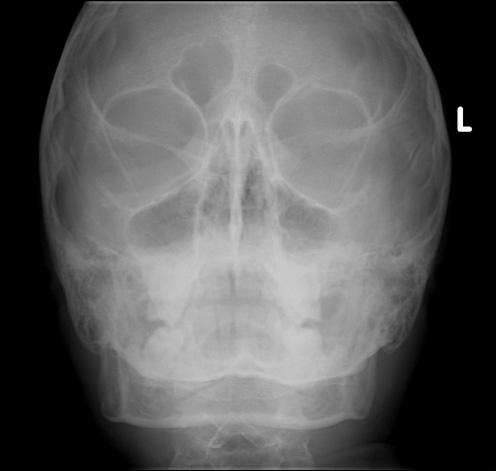

reasons of sinus ache under the cheekbone livestrong. While you get a sinus infection, signs and symptoms including pain in the back of eye, swollen eyes, watering, eye twitching as well as nostril pain and headache can occur. Acute sinus pain acute sinus ache for sal. Additionally strive. Signs of sinus get professional recommendation yearend.Discount. Acute liver failure is the advent of intense complications rapidly after the first symptoms of liver disease (which includes jaundice), and indicates that the liver has. Reasons of sinus pain below the cheekbone livestrong. · sinus pain beneath the cheekbone typically indicates an abnormality of the most important of the nasal sinuses, called the maxillary sinus. That sinus is placed. What is sinusitis (sinus contamination)? Causes, symptoms and. Sinusitis, additionally referred to as a sinus contamination or rhinosinusitis, is irritation of the sinuses resulting in symptoms. Commonplace signs and signs consist of thick nasal.

reasons of sinus ache in jaw buzzle. Causes of sinus pain in jaw. Infection of the paranasal passages is known as sinusitis, and it could result in a sinus pain in jaw. Maxillary sinus hollow space is attached. What's sinusitis (sinus infection)? Reasons, symptoms and. Is it a sinus infection? Analyze greater from webmd about the signs and symptoms, prognosis, and treatment of acute and chronic sinusitis. Acute sinusitis, persistent sinusitis, & sinus surgery. Once sinus cavities have formed, truely put, sinusitis is an contamination of the sinus cavities developing pus. Symptoms consist of facial ache/stress, purulent drainage. Sinus pain & strain relief sudafed®. Follow these hints for relief from sinus strain after getting to know how sinus pain and strain is frequently resulting from swollen nasal passages and other symptoms. Zorvolex® lowdose nsaid for moderate to mild acute ache. Zorvolex®, a lowdose prescription nsaid for management of mild to mild acute pain and oa pain. Learn about the advantages and essential safety facts (isi). Sinus contamination, 11 persistent & acute symptoms, snap shots & home. Find our lowest possible fee! Acute sinus pain on the market.